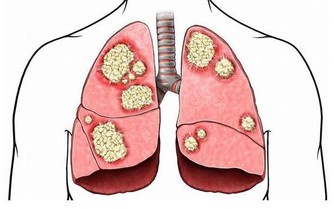

2、癌症

乳腺癌、肺癌、結直腸癌及淋巴癌等癌症在中年人群的發病率也逐年增高。